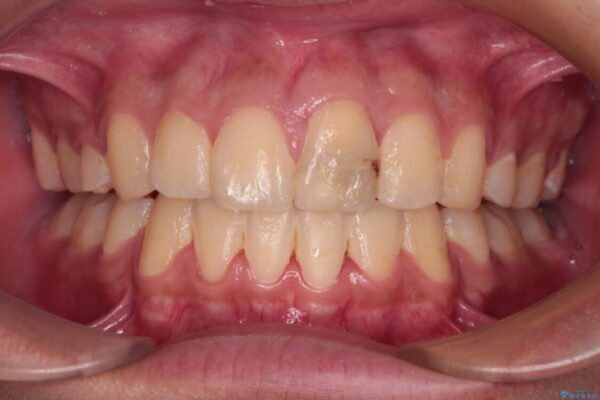

治療後について

小学生の頃に上顎前歯をぶつけ、歯の一部が破損している状態であったので、歯根が歯槽骨と癒着して移動しない可能性がありましたが、無事に治療を終えることができました。

受験勉強と重なり、舌のトレーニングが十分に行えず、高校生としてはやや長期間の治療となりました。

治療後

• 膨らんだ口元 ワイヤー装置での抜歯矯正 治療後画像